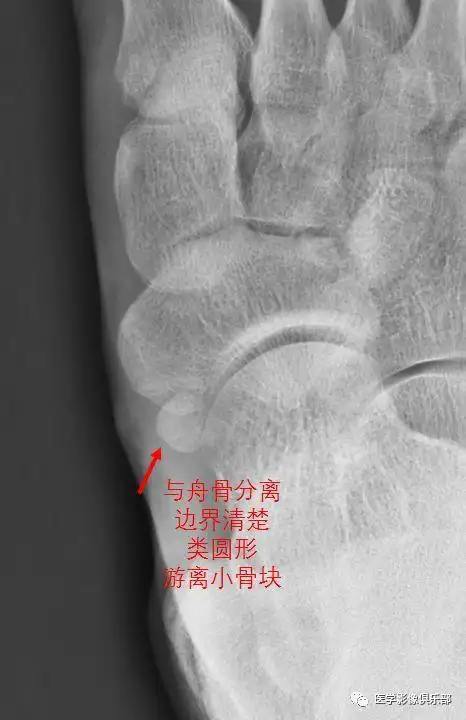

青少年足痛?当心副舟骨疼痛

足副舟骨疼痛综合症 (原创)

一例痛性副舟骨手术治疗